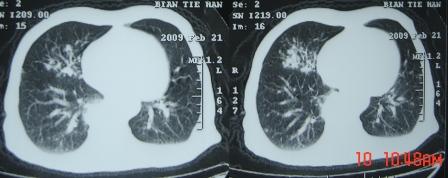

xx 男 63岁 发热 家属描述有时高热 有时低热 抗酸杆菌阴性 于2月21号 胸片及ct

右肺上叶干酪性肺炎并两肺支气管播散。

考虑右肺上叶干酪性肺炎并支气管播散。